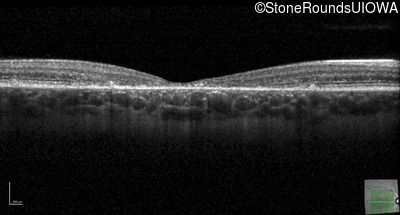

Optical Coherence Tomography - Right - 20/125 -1

Exemplar / OCT Stack

Optical Coherence Tomography - Left - 20/150